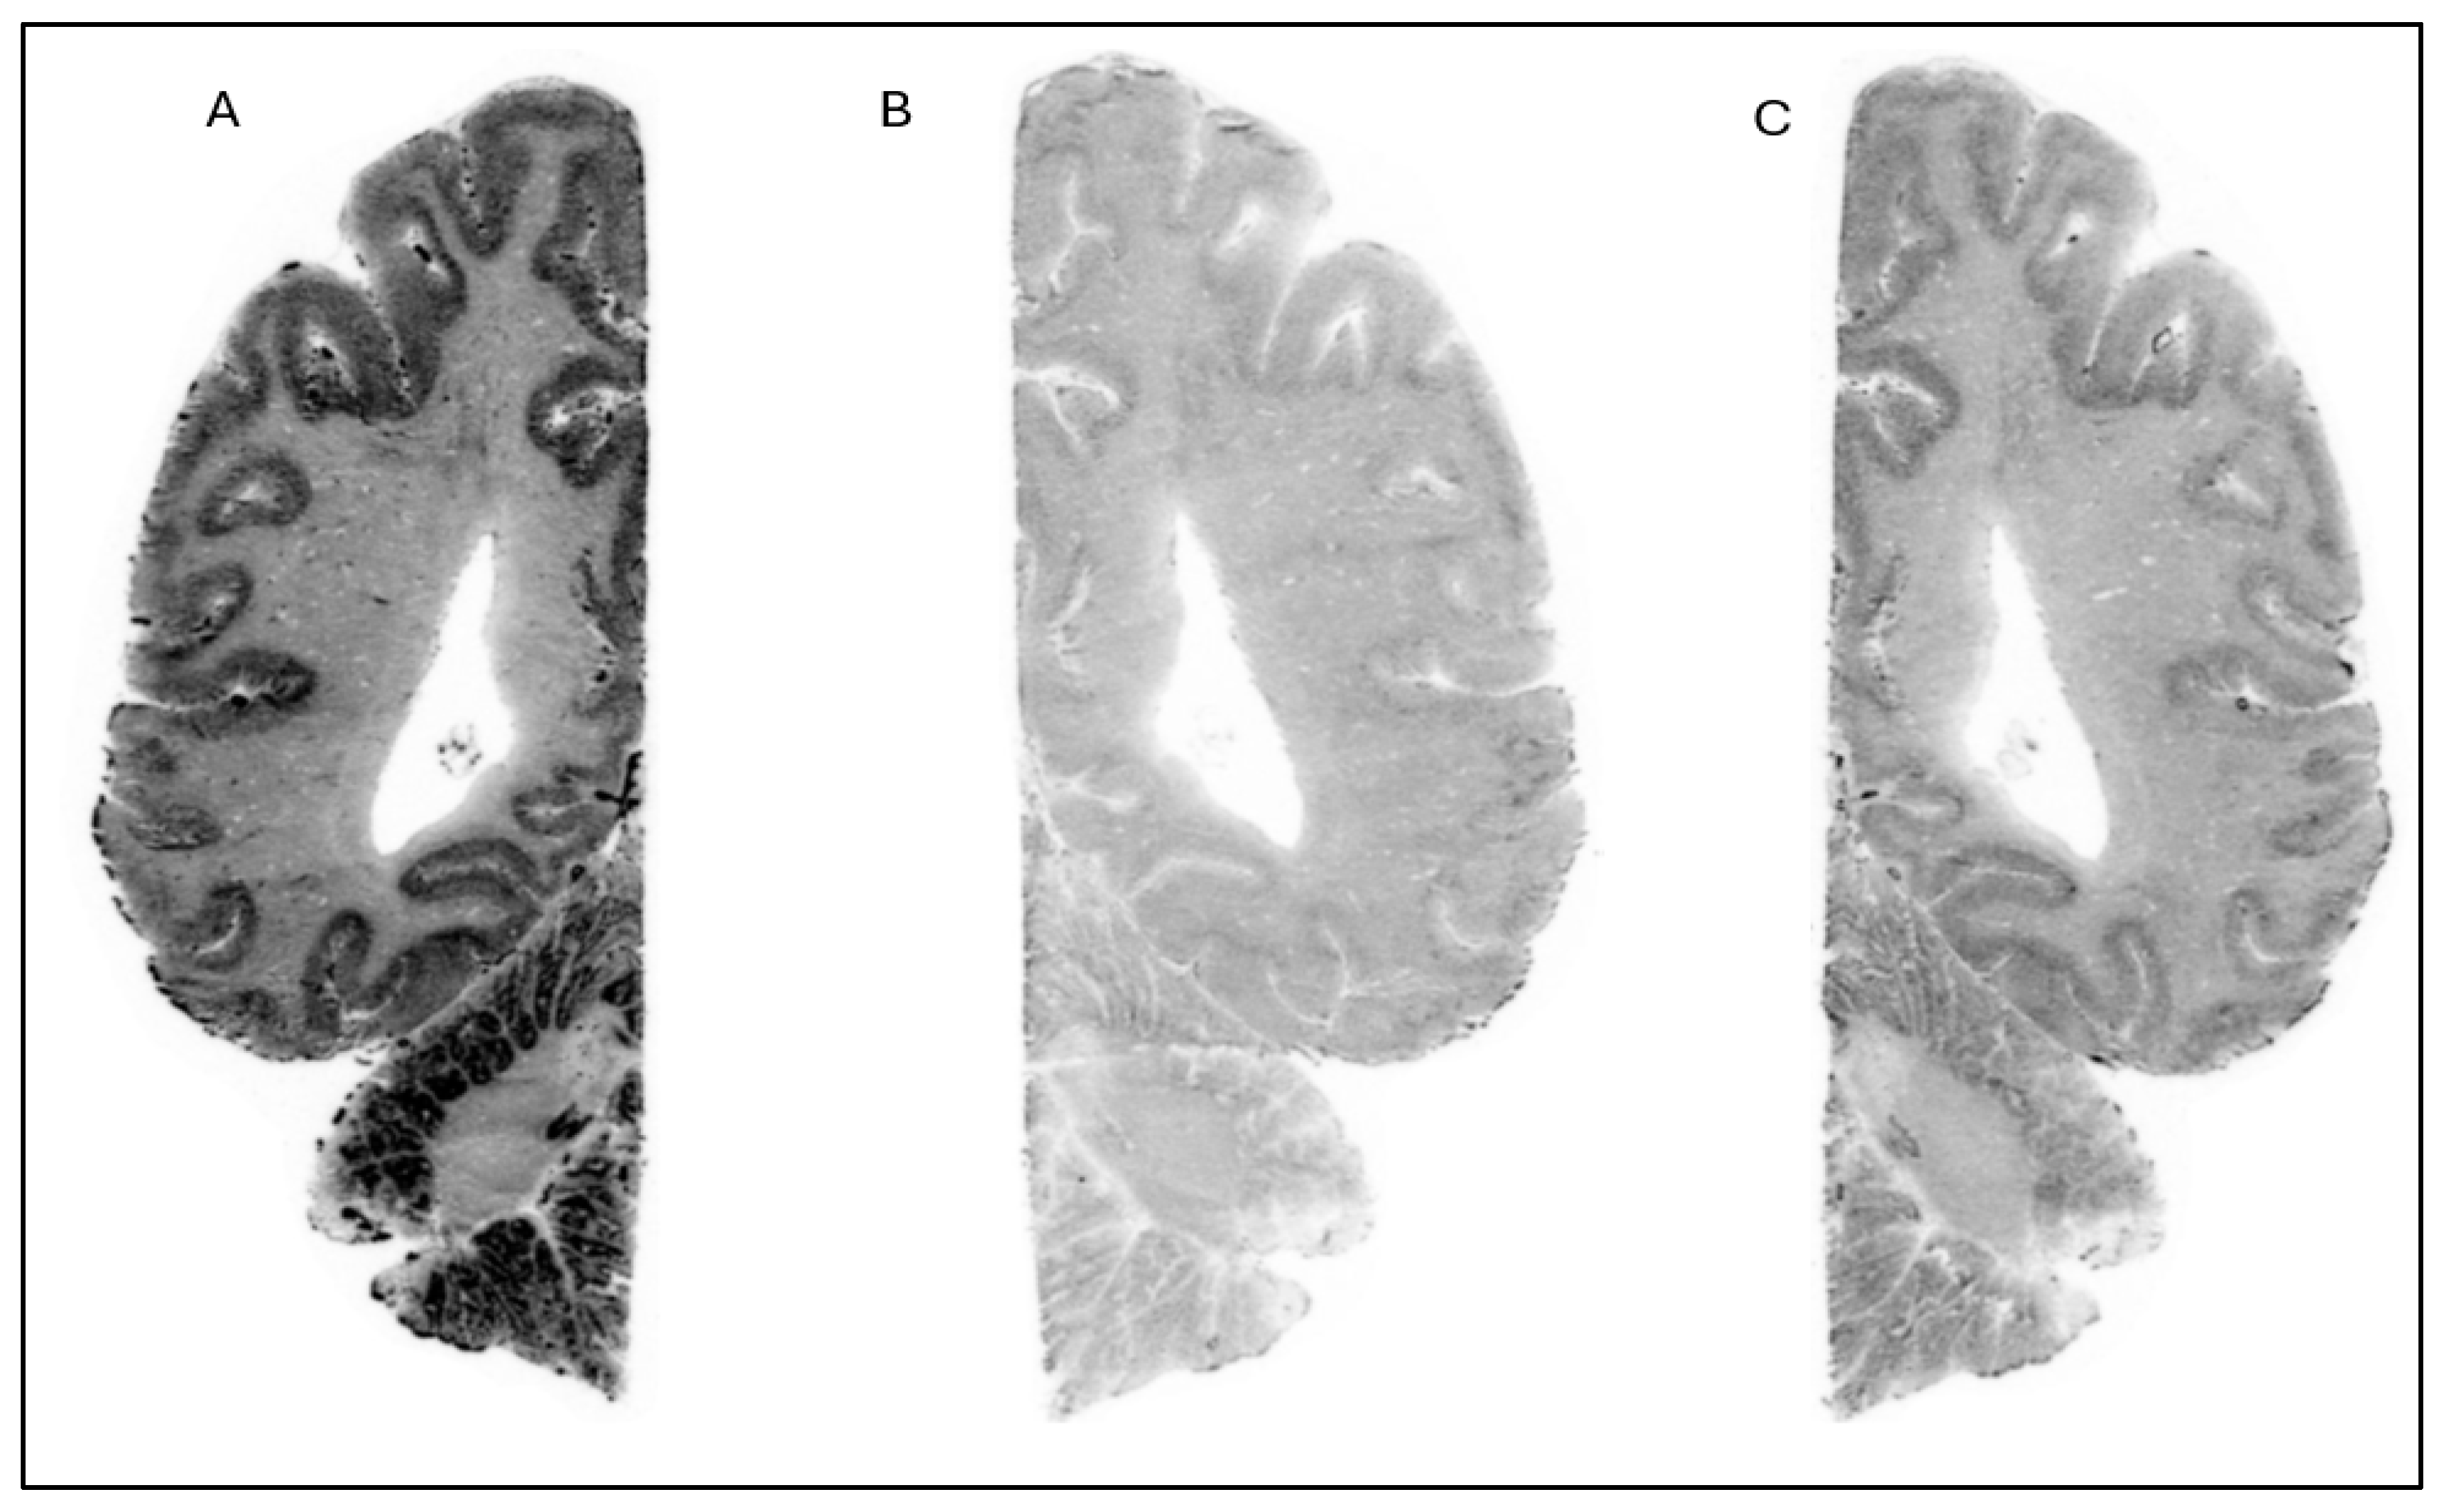

Figure 3. Autoradiograms of horizontal slices of a human brain labeled with [18F]1 at baseline condition (A) and during incubation with Compound 1 (10 µM) (B) and cold Compound 3 (10 µM) (C).

The in vitro ARG studies aimed to assess the binding characteristics of the compounds; [18F]1 displayed clear binding in brain slices from NHP (Figure 2) and human (Figure 3). The binding was effectively blocked by an excess of cold Compound 1 (self-block) as well as Compound 3 (heterologous block), indicating that its interaction with brain tissue is likely specific. However, pre-incubation with 0.1 µM of PFE-360 [20], another structurally different LRRK2 kinase inhibitor, did not significantly reduce the binding of [18F]1 in a human brain slice (Figure 4). This could indicate that [18F]1 exhibited limited specificity but more likely that the concentration of PFE-360 used may have been suboptimal, as Compound 2 demonstrated significant blocking activity at 10 µM.

In contrast, [18F]2 demonstrated a different binding profile. Its binding in human brain regions such as the striatum, hippocampus, and cerebellum was significantly reduced when sections were pretreated with 10 µM of PFE-360. The displacement of [18F]2 by PFE-360 suggests that its binding in these regions is specific to LRRK2, making it a promising candidate for further development as an LRRK2 PET imaging agent. Overall, the differential displacement profiles underscore the importance of both tracer selectivity and binding affinity in evaluating the suitability of radioligands for neuroimaging applications. Among the tested compounds, [18F]2 showed promise for targeting LRRK2 in human tissues. For radioligand [11C]3, no ARG studies were performed. Instead, we proceeded directly to in vivo PET imaging in NHPs with all three radioligands [18F]1, [18F]2, and [11C]3.